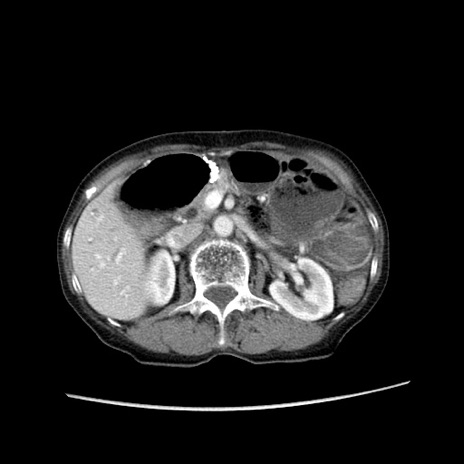

症例25(横断像)

【症例】80歳代女性

【主訴】胸のつかえ感

【現病歴】約9時間前に食後から胸のつかえた感じあり、嘔吐あり、来院。

【既往歴】胃癌(全摘)、胆摘、虫垂炎

【身体所見】心窩部に圧痛あり、反跳痛なし。

【データ】WBC 5700、CRP 0.05